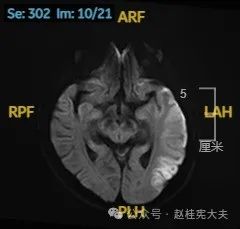

入院后给予精氨酸,左卡尼丁,辅酶Q10,维生素E等治疗。患者病情稳定好转中,2天后意识清楚,语言表达仍欠佳。当天复查颅脑磁共振如下:

以上为患者发病后3次的颅脑磁共振片子,临床诊断基本上可以确认了,希望患者逐渐恢复!